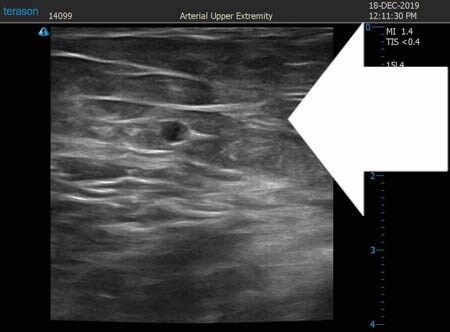

ここではふくらはぎの術中変化を

紹介しましょう。

患者様のふくらはぎは筋肉質。

なかなかダイエットのみでは

細くなりにくいふくらはぎでしたから

徹底的に皮下脂肪を根こそぎ

患者様には満足していただけるように

頑張りました。